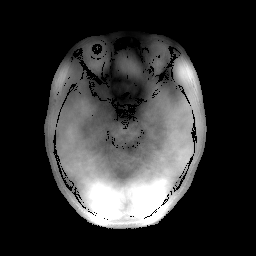

In the first set of evaluations, we considered the reconstruction of an MR image from -undersampled k-space data. The gold-standard magnitude and phase images, which were obtained from a real fully-sampled in vivo T1-weighted MRI acquisition with in-plane matrix size, are shown in Fig. 1. This figure also shows the k-space sampling mask (corresponding to undersampling) that we used to simulate an accelerated acquisition.

For this simulation, the original fully-sampled k-space data (originally measured with 32 channels) was coil-compressed down to 8 virtual channels to reduce computational complexity, and was then retrospectively undersampled using the aforementioned k-space sampling mask. For reconstruction, the matrix was chosen according to the standard SENSE model [41], with sensitivity maps estimated using ESPIRiT [42]. The magnitude regularization took the form of an penalty as given by Eq. (40), where, following Ref. [8], the sparsifying transform was chosen to be the unitary Daubechies-4 wavelet transform. The phase regularization took the form of a Huber-function penalty as given by Eq. (41), where the Huber parameter was chosen to be a small number (i.e., ) in order to approximate the -norm. Following Ref. [8], the transform we used for phase regularization was also a unitary Daubechies-4 wavelet transform. All three algorithms were initialized by applying SENSE-based coil-combination to the multi-channel images obtained by zero-filling the unmeasured data.